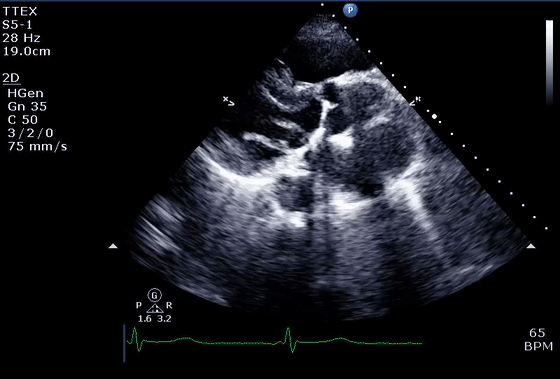

8、心脏器械之人工瓣膜

植入式心脏设备,如起搏器和植入式心律转复除颤器导线、导管、机械循环支持设备和人工瓣膜,通常代表强反射体,容易出现上述反射相关伪像(反射或彗尾、阴影和镜像)以及旁瓣和波束宽度伪像。因此,心脏设备使超声心动图图像的解读变得复杂(图8),需要从不同的成像角度仔细检查设备和周围结构。

彩超伪像是什么心脏超声伪像有哪些?如何识别它们?_https://www.jmylbn.com_新闻资讯_第27张图 8 心脏装置作为图像伪影的来源。

(A)人工机械二尖瓣下方的多个混响和彗尾(箭头)以及瓣环下方的两个声学阴影区域(星号)(视频 11)。(B) 植入 MitraClip 装置(箭头)远端的声学阴影(星号)。还要注意血流信号的阴影,这可能会导致低估二尖瓣反流量。(C) 右心房 (RA) (箭头) 中的起搏器导线,导线下方有线性彗尾混响 (箭头),旁瓣伪影沿径向延伸。(D) 右心室 (RV)(箭头)中的除颤器导线,具有穿过解剖边界(室间隔)的线性弧状旁瓣伪影。这不应被误解为错位(穿孔)导线进入左心室腔(视频 12)。